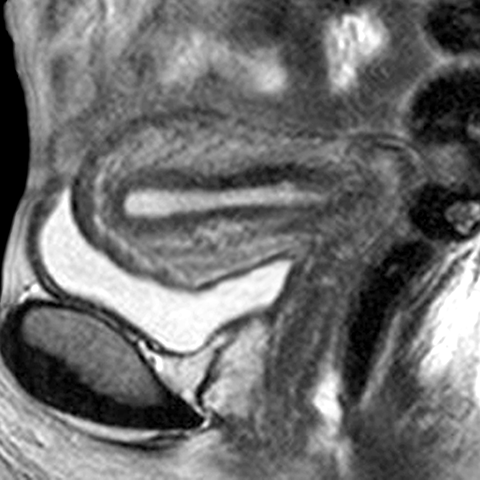

Uterus (T2 weighted MR, sagittal) [2 of 4]